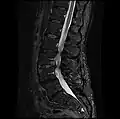

MRI lumbar spine pre-hemilaminectomy (sagittal T2 FRFSE)

-

MRI lumbar spine pre-hemilaminectomy (sagittal T1 FSE)